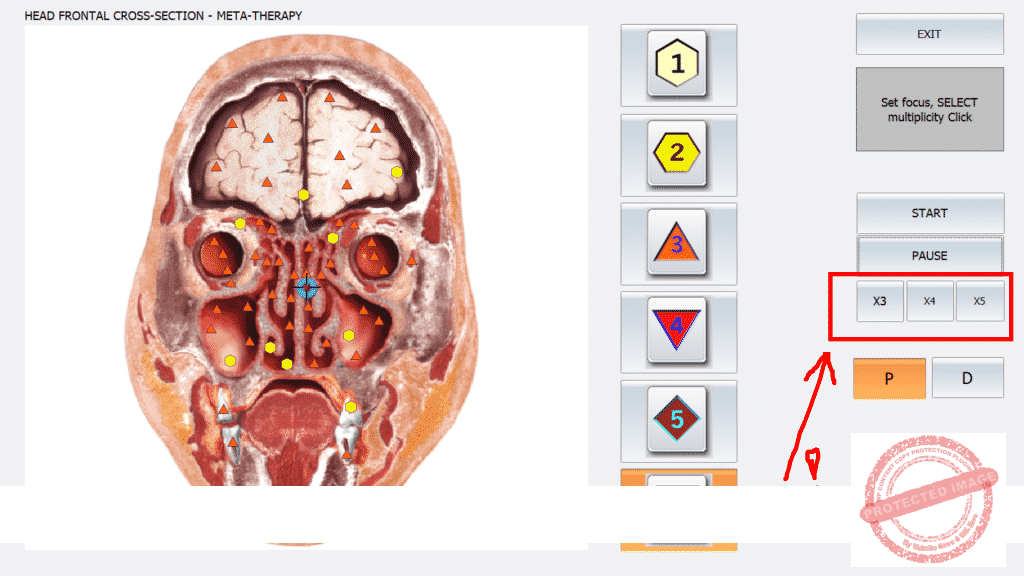

+ Multiple META therapy !!!!

*A preview of The ISHA METATRON PRO, the most powerful for microscopic INDEPTH scans and treatments

ISHA Metatron Pro, for indepth auto find sources of the problem/dis ease with the I3 function and microscopic treatments as teached in the ISHA Classes. As you can see and hear in the globals ISHA classes, a doctor from Serbia confessed. It is the most powerful and stable version on the market. All professionals do agree, IT IS the most powerfull version ever created, period !) Why, well, because of many reasons. For expample: instead of doing 50-100 times to get results on the nidis. With this ISHA Metatron, you will get the same results in 3-5 times treatments (it is life recorded, so you can see for yourself). No errors and the most extended libraries aka etalons from many healing modalities and remedy origins.